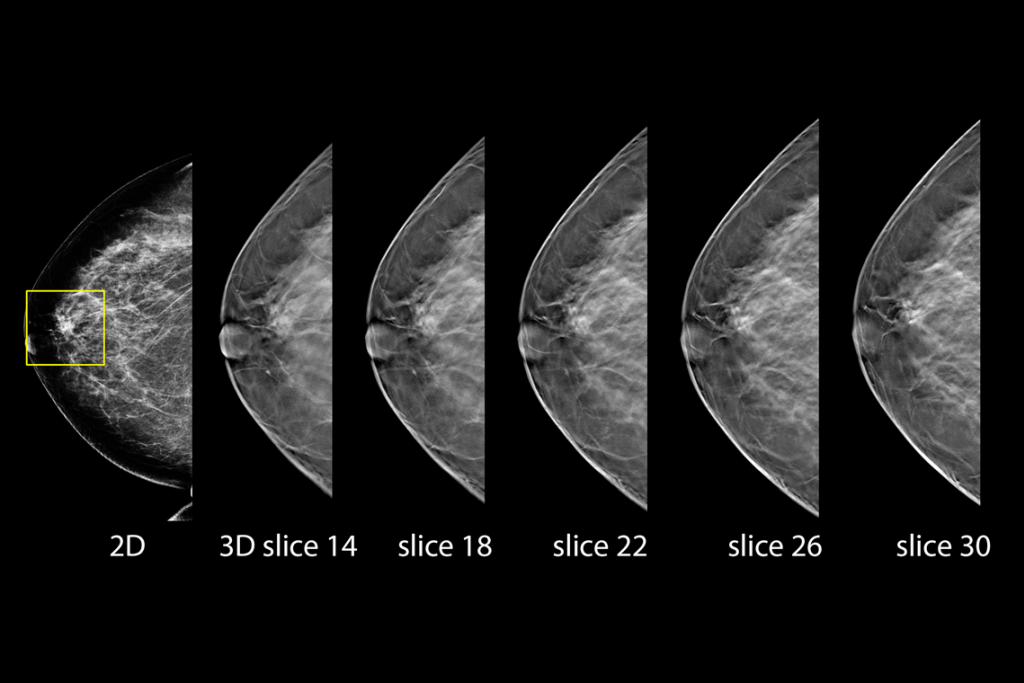

Imagens clínicas de mamografia com lesão suspeita